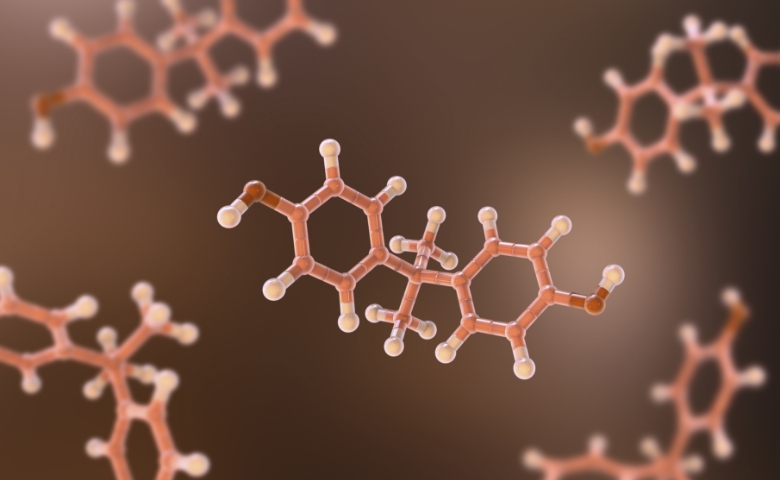

JS트로겐의

갱년기 치료 효과

에스트로겐 수용체 조절로

갱년기 및 호르몬 부작용 완화

JS트로겐이 갱년기 증상 완화를 돕는

에스트로겐 베타 수용체(ERβ) 활성화

JS트로겐이 호르몬 부작용을 유발하는

에스트로겐 알파 수용체(ERα) 억제